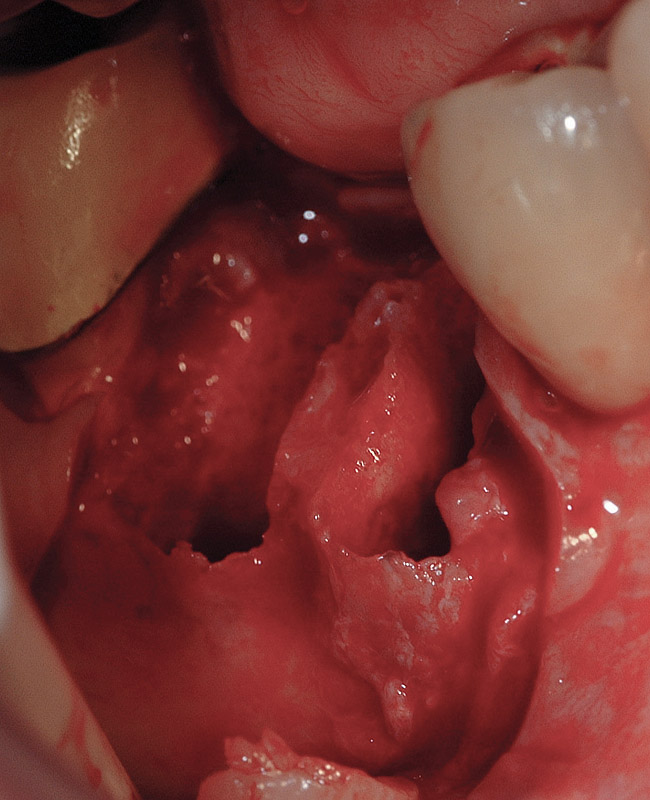

Implant placement at the time of mandibular molar extraction should never be attempted if there is any doubt about the ability to place an ideal dimension implant in the appropriate restorative position and attain primary stability. In such a situation it is better to first perform regenerative therapy at the time of tooth removal and place the implant in a subsequent surgical session (Figure 2 through Figure 4).

All mandibular multi-rooted teeth are hemisected (or trisected in the rare cases of three-rooted mandibular molars) prior to removal. In such cases, a piezosurgical approach is utilized, in conjunction with specifically designed periotomes, to effect atraumatic tooth extraction. If such therapy is performed appropriately, the net result is an extraction socket whose alveolar morphology has been no further compromised through the act of tooth removal. In situations where high-speed rotary instrumentation must be used to help retrieve fractured root portions, the site is deemed no longer amenable to immediate implant placement due to the excessive trauma having been placed on the alveolar bone in the area. Regenerative therapy is performed employing appropriate graft materials and covering membranes, and the implant is placed in a second surgical visit. Such instances are rare.